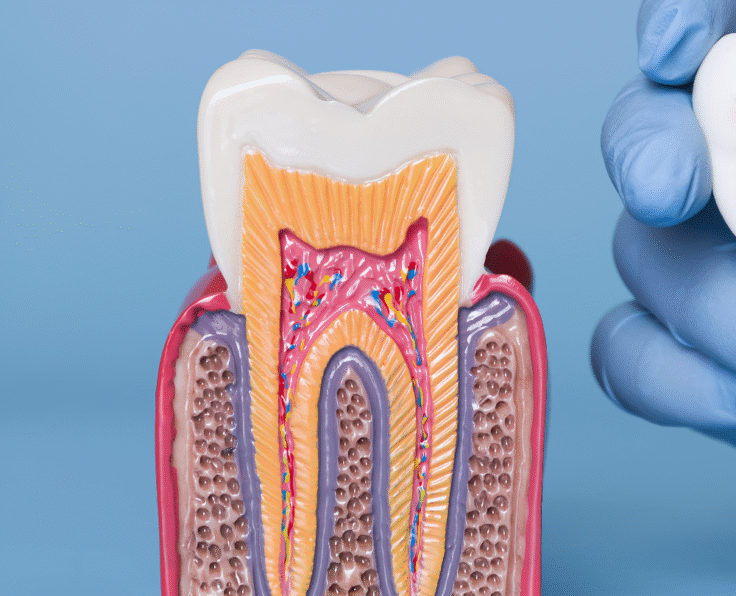

Our Advanced Dental Treatments

Dental Implants

Dental implants offer a strong, permanent replacement for missing teeth, ensuring a natural appearance and long-lasting oral stability.

Our Dental Services

Our Treatment Process